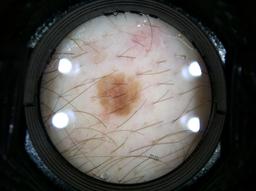

Biopsy-confirmed melanocytic and non-melanocytic skin lesions. This dataset includes over 500 melanomas. Many images have polarized and contact variants.